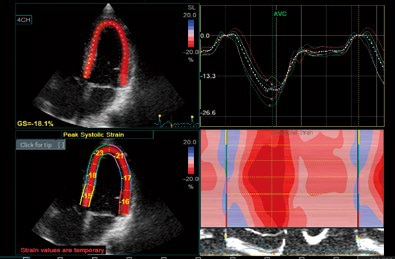

AFI

心尖部画像を基に心筋のスペックルをトラッキング。

局所心筋壁運動の程度とタイミングを簡単に評価できます。